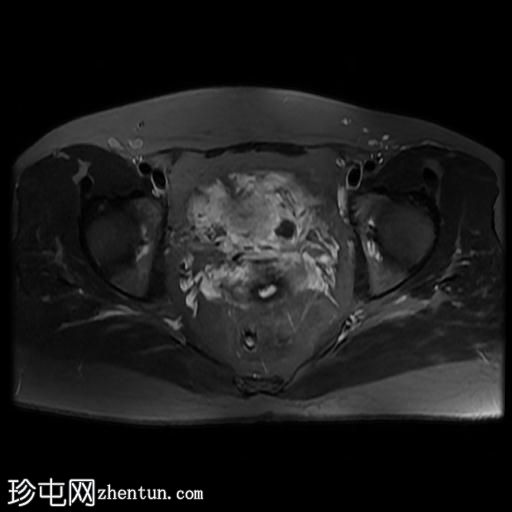

轴位

T2加权像

盆腔MRI显示双侧子宫旁多条迂曲静脉,自子宫肌层延伸至盆腔。

此外,左侧附件可见两个充满液体的单纯性囊肿,大小分别约为31 mm和32 mm;右侧附件可见一个卵泡囊肿,大小约为19 mm。

影像学特征符合盆腔充血综合征的诊断,患者为35岁女性,有慢性盆腔疼痛和痛经病史。